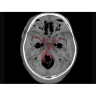

Позволяет проводить комплексные исследования всех анатомических зон, включая нейровизуализацию, ангиографию, исследования органов грудной и брюшной полости. Особенно эффективен для раннего выявления онкологических заболеваний.